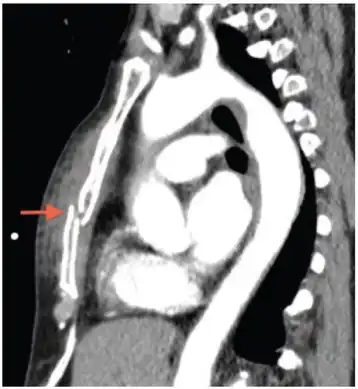

Computed tomography identifying displaced sternal fracture.

X-rays of the chest are taken in people with chest trauma and symptoms of sternal fractures, and these may be followed by CT scanning.[12] Since X-rays taken from the front may miss the injury, they are taken from the side as well.[13]